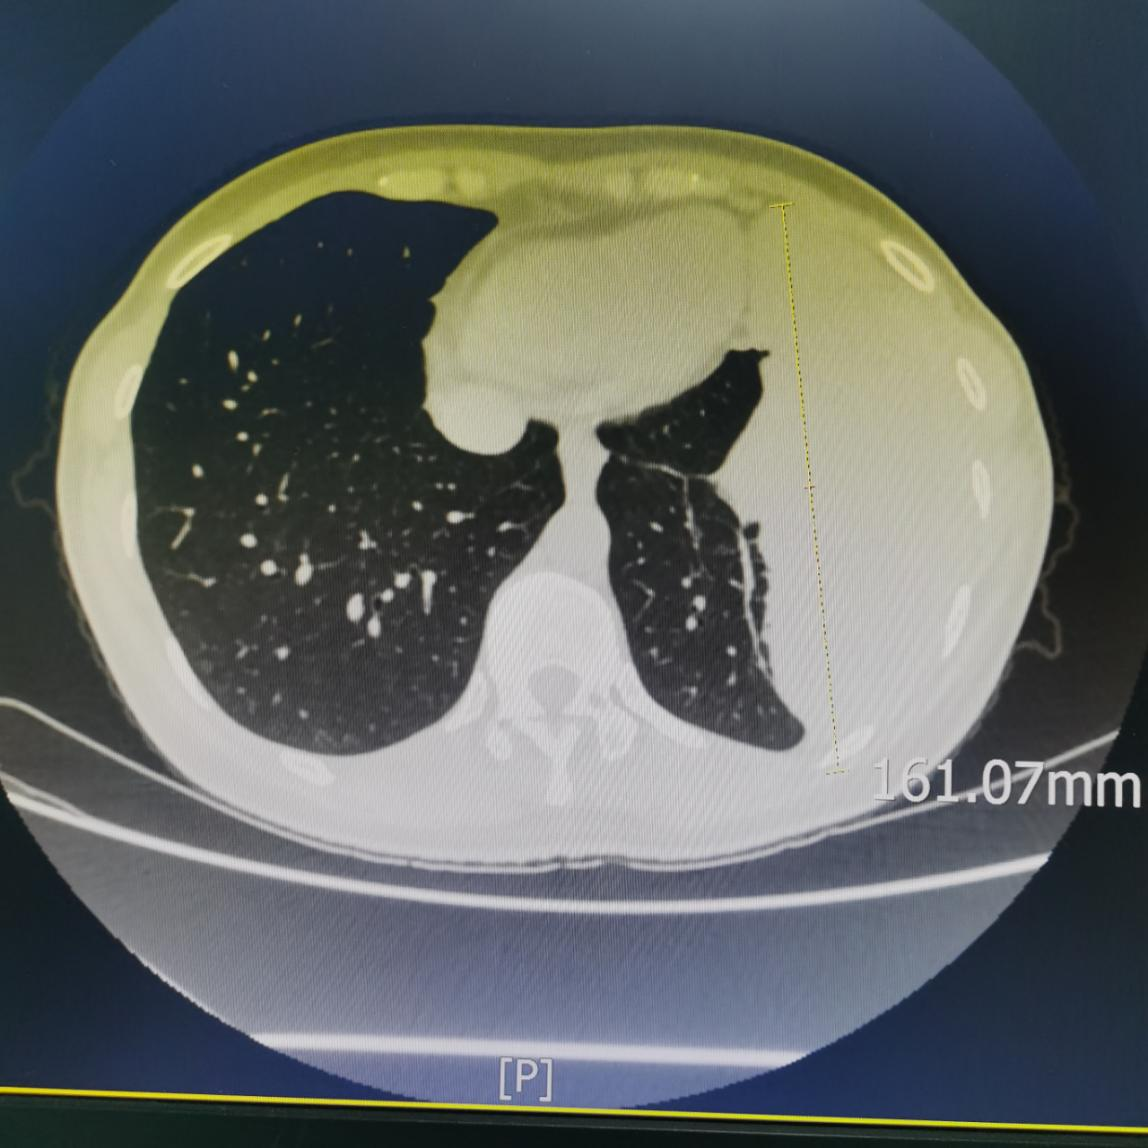

患者入院后,进一步完善胸部增强CT扫描,结果示:左侧胸腔见团块状高密度影影,范围大小约146mm×64mm×101mm,与邻近胸膜呈宽基底连接,边界不清,其内密度不均,增强扫描动脉期见呈结节、斑片状明显强化,大结节内可见斑片状无强化区,部分病变未见强化,病变内可见增粗、迂曲强化;静脉期病变强化范围较前片增多、增大,呈持续性明显强化,大结节呈填充强化,中央低密度未见强化;邻近左肺可见斑片状高密度影,增强扫描呈明显强化。提示:左侧胸腔占位,考虑起源胸膜,以胸膜孤立性纤维肿瘤可能性大。同时完善胸部增强磁共振扫描(磁共振对软组织病变分辨率更优),同样考虑胸膜来源孤立性纤维肿瘤可能性大。

胸部增强CT检查是左胸腔巨大占位